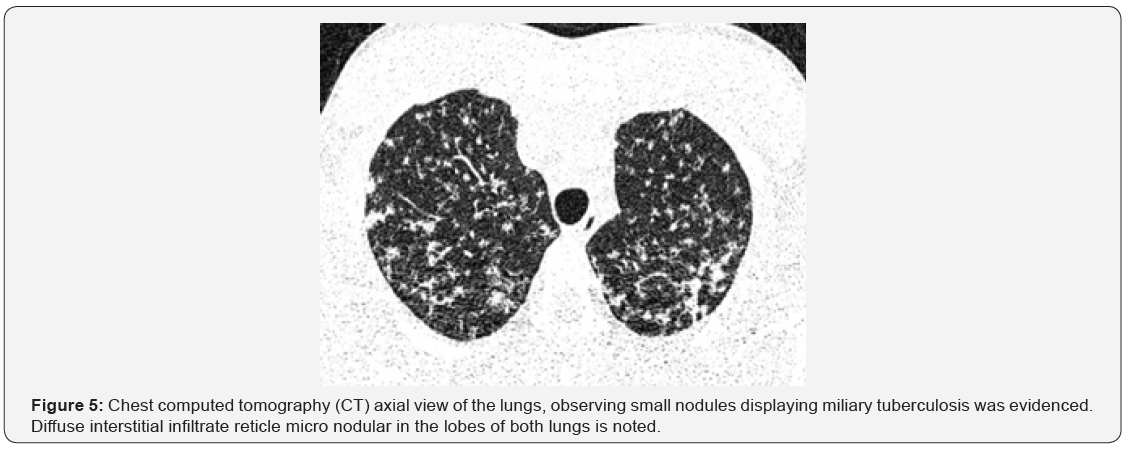

Tomography